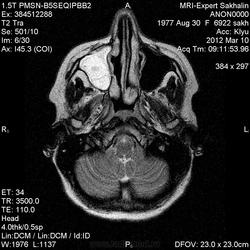

Направительный диагноз:головная боль напряжения.

Краткий анамнез заболевания, жалобы: головные боли,снижение памяти, раздражительность, снижение аппетита в течение 3-х месяцев.

Подозреваю демиелинизацию,гиппокампальный склерз ( тогда базальные ядра и ножки при чем?),ишемические проявления -не знаю!Помогите , пожалуйста, начинающему доктору!

Лимбический энцефалит? Паранеопластический процесс? А где диффузионные программы- не помешают. Нужно подумать (или спросить у ннемо, например))).

Написала дифф.ряд: лимбический энцефалит, лимфому ЦНС, герпетический энцефалит.

С лимфомой верифицированной не встречался, картина не противоречит паранеопластическому или герпетическому энцефалиту. Склероз гиппокампов: нет уменьшения их размеров, зоны изменений сигналов гиппокампами не ограничиваются, есть кроме височных долей и в ножках мозга, опять же накопление контраста.

Женщина 1977 года рождения.Со слов мужа , около 3/х мес. назад начались головные боли, снижение памяти, раздражительность снижение аппетита.Перенесла какую-то инфекцию типа ОРЗ.С ней разговаривать трудно-мало что помнит.На асоциальную , наркоманку не похожа-приличная с виду женщина.Неврологический статус хотела выяснить у лечащего врача по телефону, но она живет в районе,и телефон не указала .Визуально-неврологический статус без особенностей.В направлении-головная боль напряжения .Нет указаний -на что обратить внимание.

Еще гайморит тут правосторонний, может это несколько качнет весы в сторону воспалительного процесса?

Ишемические изменения и темпоральный склероз - нет.

Есть и давно подтвержденное понятие паранеопластический лимбический энцефалит - как вариант примерно так и будет выглядеть.

В данном случае больше данных за воспалительный энцефалит - есть синусит (не нравиться гиперинтенсивное включение парацентрально в пазухе -грибок????) .

С учетом накопления контраста да и по локализации однозначно не опухоль, не инсульт, не травма. Из классики да действительно герпес любит виски, также и иные вирусные могут быть (этиологию иной раз не угадаешь - бессмыслено), может быть и тбс. но сос четов не сбрасывал бы паранеопластический - тем более женщина да и контраст накопила как бы не молочка?? Ну и совсем чтоб запутать нет ли В20? только на внешний вид и на мужа не надо ориентироваться - у нас и у врачей и у студентов мед вузов бывает - пройденный этап(((

Была у нас пациентка (картинки предоставить не могу , так как поезд ушел) , картина была один в один , только в меньшей степени выраженности. Тоже возникло после перенесенной ОРВИ, после лечения приходила на контроль - мр- сигнал вернулся к норме. Так что согласна с энцефалитом. При паранеопластическом процессе все же более четкие границы , я так думаю. и распостраненность несколько другая..